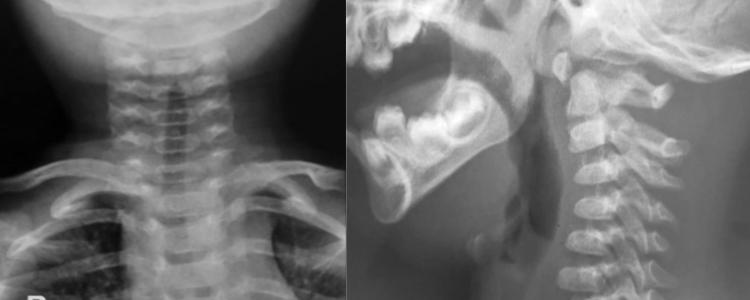

Radiografía de columna cervical frente y perfl

Se presenta un caso poco frecuente de espondilolisis cervical de C2, en un lactante de 1año y 7 meses de edad. Con el objetivo de mostrar las difcultades diagnósticas y terapéuticas, conociendo aquellos signos radiológicos que permiten identifcar esta infrecuente patología así como el algoritmo diagnóstico. Se optó por un tratamiento conservador con collarete, y se controló de forma regular obteniendo una muy buena evolución.

La espondilolisis cervical se define como una hendidura del istmo vertebral o espacio existente entre las faceta superior e inferior de los pilares articulares. Mientras que a nivel lumbar se ha descrito en el 5% o 6%de la población mundial a nivel cervical se considera una anomalía rara, con menos de 100 casos publicados hasta la fecha.